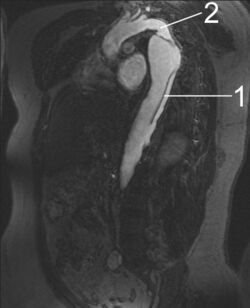

MRI of an aortic dissection

1 Aorta descendens with dissection

2 Aorta isthmus